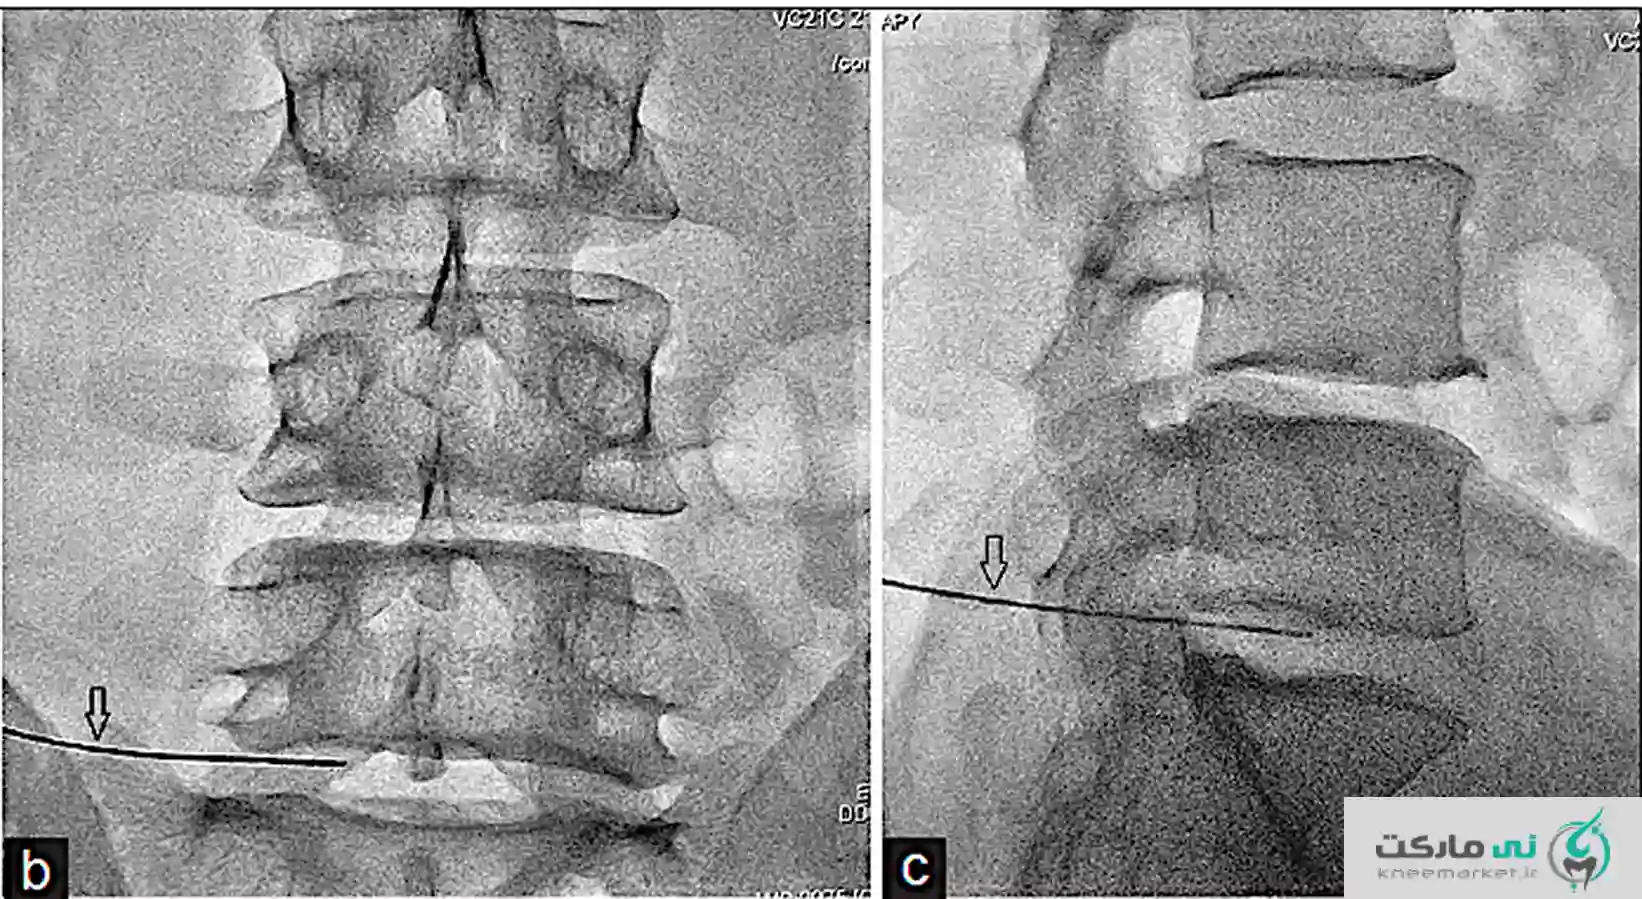

اوزون تراپی یا درمان با گاز اوزون روشی جدید است که در آن از گاز O3 و تزریق آن به محل درد، برای درمان بیماریهایی مانند دیسک یا فتق کمر استفاده میشود. تزریق اوزون به ستون روشی کم تهاجمی برای افرادی است که از درد ستون فقرات رنج میبرند و بهدنبال راهی سریع برای درمان این بیماری هستند. این روش درمانی در هر مرحلهای از بیماری دیسک کمر قابلاستفاده خواهد بود و خبر خوب این است که احتمال موفقیتآمیز بودن درمان با این روش، بیش از 70 درصد است. برای آشنایی بیشتر با تزریق گاز اوزون برای دیسک کمر با این مطلب از سایت نی مارکت همراه باشید.

تزریق گاز اوزون برای دیسک کمر